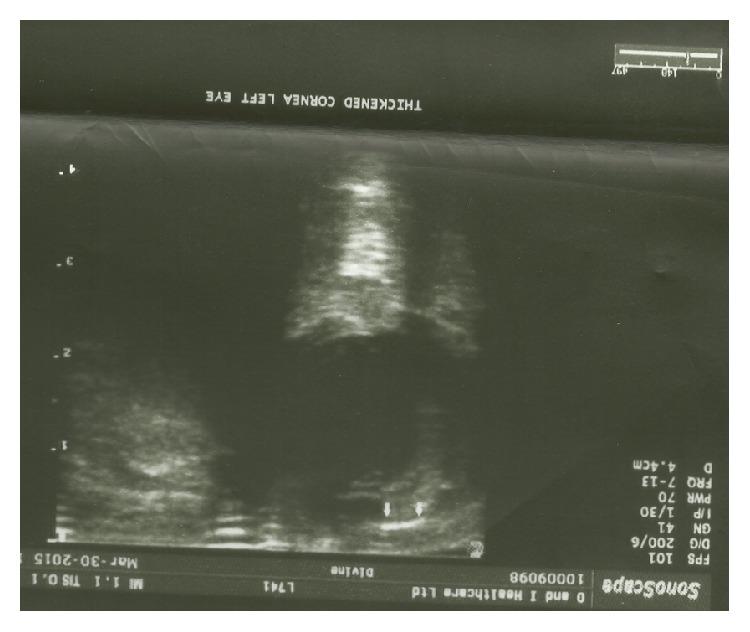

Background. Delayed postoperative suprachoroidal hemorrhage (DSCH) may occur following intraocular surgery for the treatment of glaucoma. It is considered to be a rare and debilitating event if not managed appropriately. Reported herewith is a case of Primary Congenital Glaucoma followed by DSCH with successful immediate surgical intervention and visual restoration. Patient and Method. An 8-month-old male child had bilateral Primary Congenital Glaucoma (PCG). Combined Trabeculotomy Trabeculectomy with 5-Fluorouracil (5FU) was performed. He developed delayed suprachoroidal hemorrhage (DSCH) within 24 hours after intraocular surgery which was drained. In addition, he developed exposure keratopathy and left amblyopia. Outcome. Resolution of the DSCH was seen with surgical drainage in addition to treatments for exposure keratopathy and amblyopia. These resulted in reduced intraocular pressure and improved visual acuities. Conclusion. There appears to be a difference in the overall management of PCG and DSCH between adults and children. A high index of suspicion as well as emergency surgical treatment for DSCH and associated conditions should be performed on pediatric patients that present with these challenges.

背景。青光眼眼内手术后可能发生术后迟发性脉络膜上腔出血(DSCH)。如果处理不当,它被认为是一种罕见且使人衰弱的事件。本文报告一例原发性先天性青光眼继发DSCH,经立即手术干预成功并恢复视力的病例。患者与方法。一名8个月大的男童患有双侧原发性先天性青光眼(PCG)。实施了联合小梁切开小梁切除术并使用5-氟尿嘧啶(5FU)。他在眼内手术后24小时内发生了迟发性脉络膜上腔出血(DSCH),随后进行了引流。此外,他还出现了暴露性角膜病变和左眼弱视。结果。除了对暴露性角膜病变和弱视进行治疗外,通过手术引流使DSCH得到缓解。这些措施降低了眼压并提高了视力。结论。成人和儿童在PCG和DSCH的整体管理上似乎存在差异。对于出现这些问题的儿科患者,应保持高度怀疑,并对DSCH及相关病症进行紧急手术治疗。